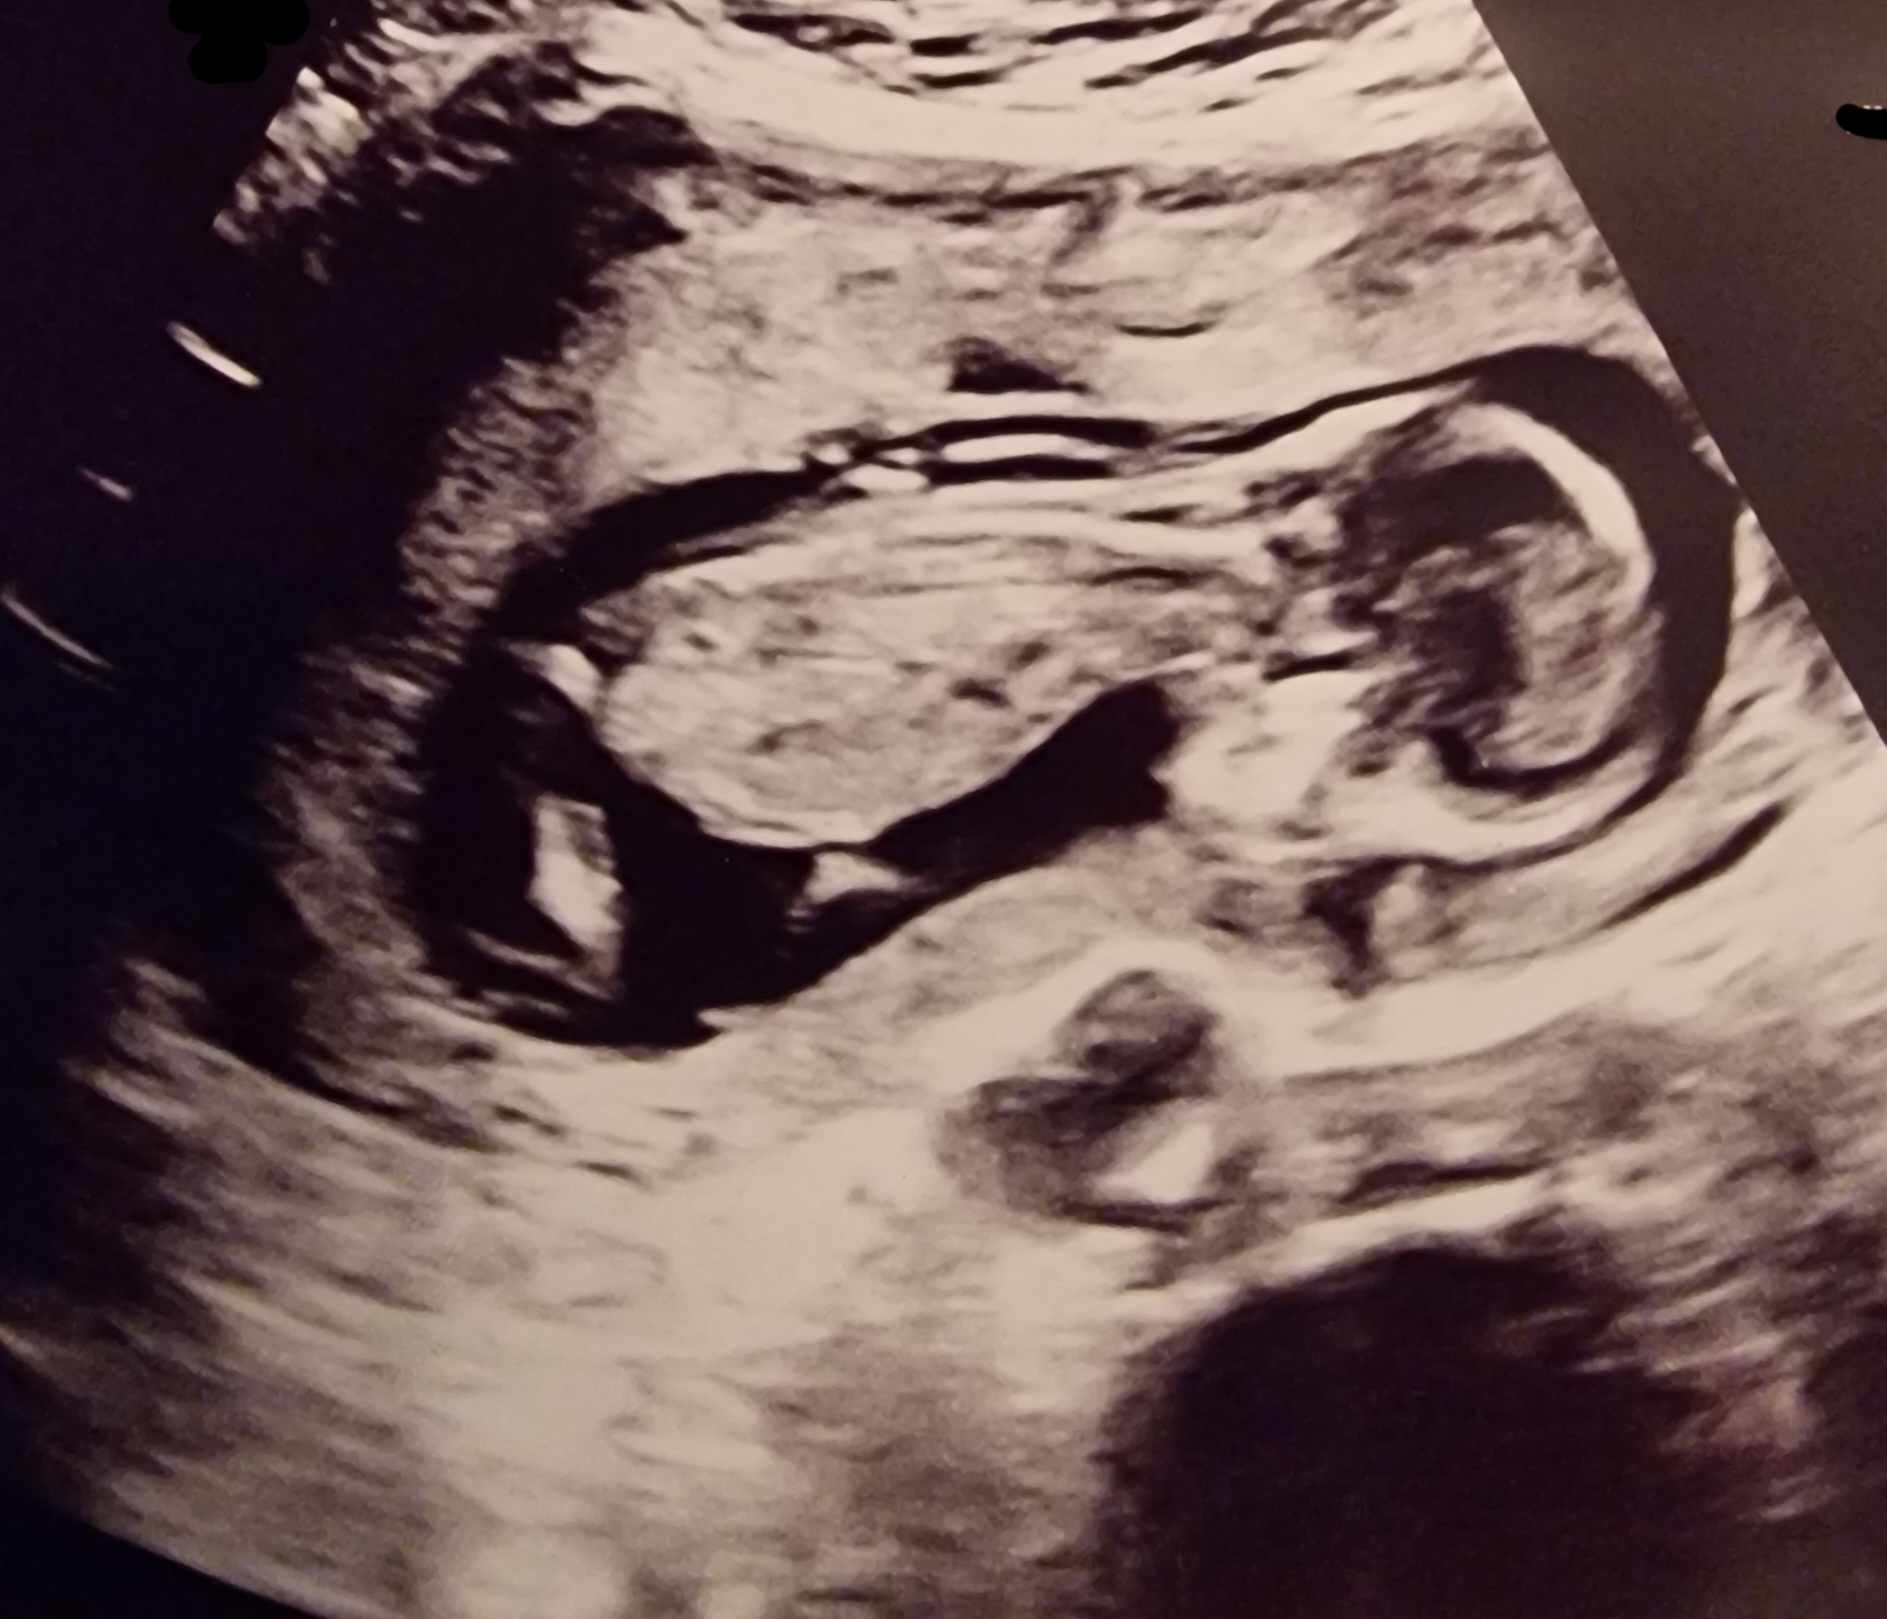

Gravid: 14+0

Termin: 01.07.26

Stadig et mysterium hvem som skjuler seg i magen, men jordmor v/Bærum sykehus mistenker en gutt enn så lenge. Hadde vært toppers for bror som drukner i kusiner i tillegg til storesøsteren

Vis vedlegget 476610